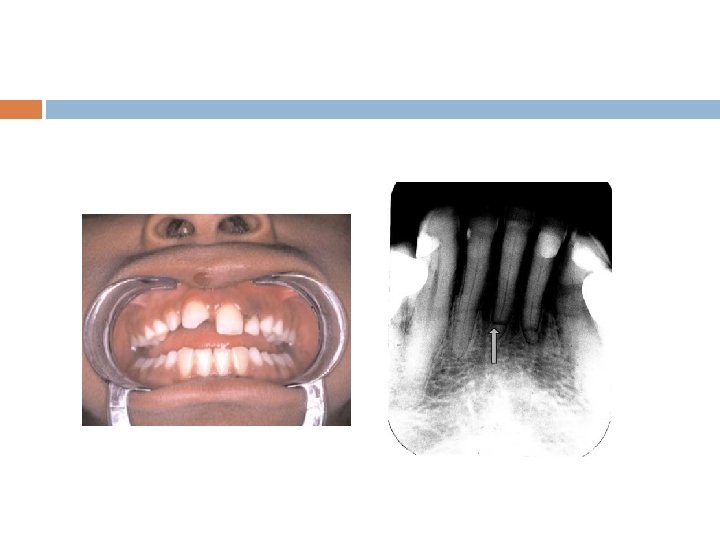

Prevertebral Space Infection(lateral view)

X-ray neck P. A. View : Showing severe acute deviation of trachea to Rt. side